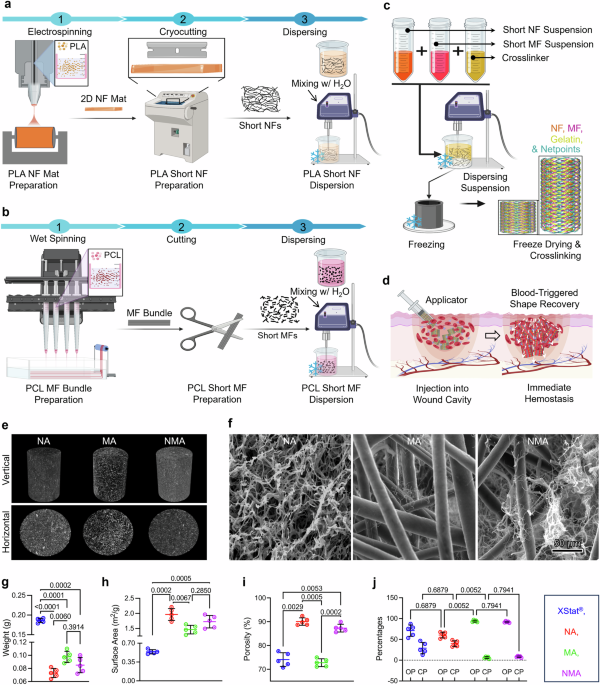

During this study, we adopted a neural network structure [19, 20] that was designed based on the faster R-CNNs [21] (Fig. 3). The neural network was composed of two main subnetworks: region proposal network and region-based CNN. During the first stage, the region proposal network approximately detected lesion candidate regions in the input image and was composed of “feature extraction layers” and “region proposal layers.” IoU is an index that is calculated by using a bounding box that is delimited as the smallest rectangle of the lesion inferred by AI and a correct-answer bounding box that is delimited with the smallest rectangle of the correct lesion (ground truth annotated as the correct answer) in order to calculate the degree of intersection between the rectangles as follows.

Overview of the structure of the detection network. “Feature extraction layers” extracted features from CT colonography data, which are 3D image data, using 3D convolution. “Region proposal layers” obtained lesion candidate regions from the features. During the second stage, region-based CNNs accurately determined whether each candidate region detected during the previous stage was a target lesion and was composed of “region of interest align” and “region classification layers”. “Region of interest align” resized the features of the detected lesion candidate regions to a fixed size, and “region classification layers” determined whether each lesion candidate region was a lesion. 3D: three dimensional; RCNN: region-based convolutional neural network; RPN: region proposal network.

The aforementioned network was trained during this study using two groups of datasets with different characteristics as learning datasets. The data from the previous two trials primarily consisted of small lesions. In contrast, the Saitama and Tonan datasets included only large lesions as learning targets, excluding small lesions. When the algorithm, trained on both large and small lesions together, was tested on the Saitama and Tonan datasets, there was a possibility that its performance in detecting small lesion would decrease. We avoided this problem by training the neural network using the following two patterns: the pattern that included the Saitama and Tonan datasets as training data and the pattern that did not include these datasets. Furthermore, the neural network trained on the data of the two previous trials was prepared using the same data. We integrated the outputs of these three different neural networks with the inference (Fig. 4).

Schema of the process of integrating the outputs of three different neural networks. The first is a neural network trained on data from two previous trials with many small lesions and data from Saitama and Tonan with mainly large lesions. The second is a neural network trained on data from Saitama and Tonan. The third is a neural network trained on data from two previous trials. A trained model will have slightly different characteristics even with the same training data and same neural network; therefore, it is known that accuracy can be improved by using many trained models to obtain the final result by majority vote, which is called AI ensemble learning. RCNN: region-based convolutional neural network; RPN: region proposal network.